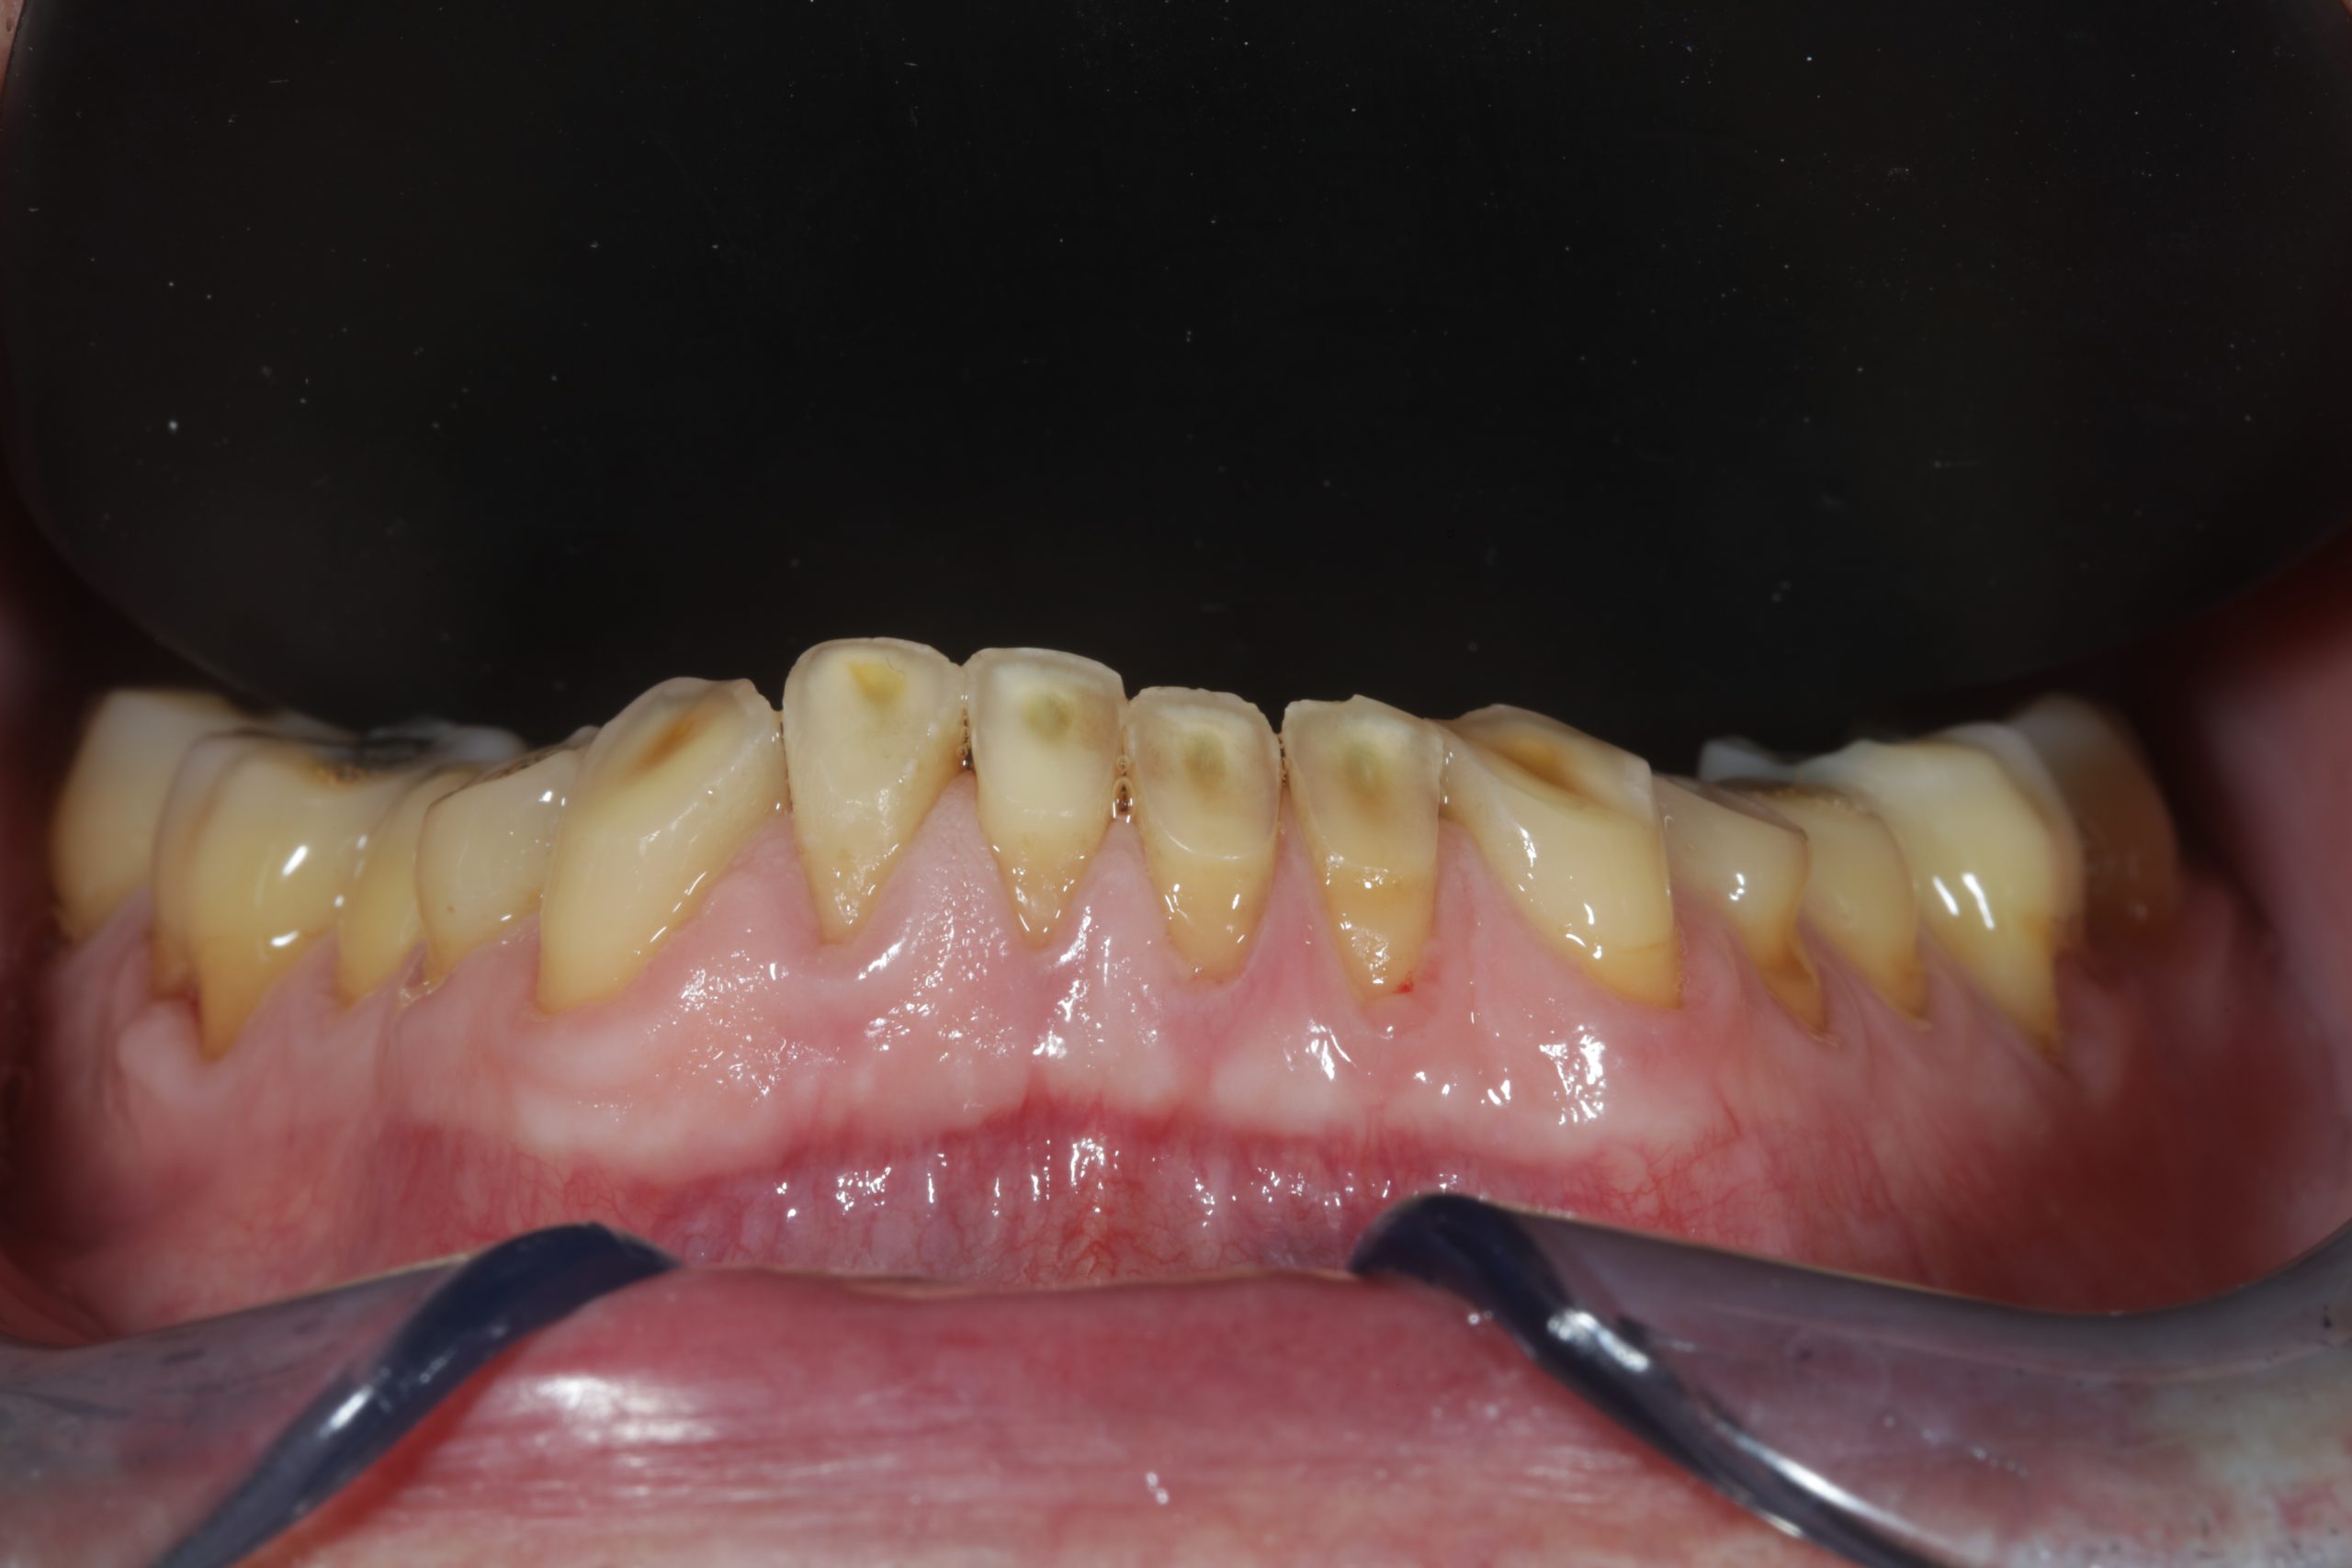

Total upper and lower rehabilitation using CDP technology as an analysis and planning tool

Case study carried out with Athena Smile Pelekanos (GR ) : dott . Stavros Pelekanos